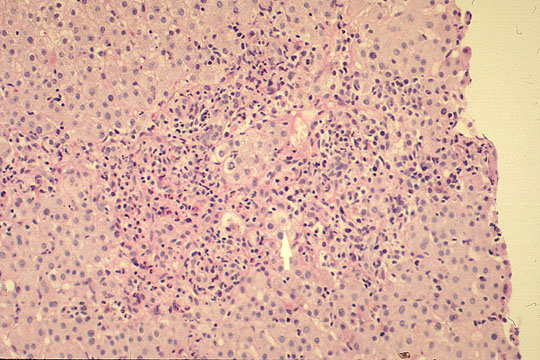

PATHOLOGY

Portal and periportal inflammation

Fig 89 - PORTAL AND PERIPORTAL INFLAMMATION: Presence of both lobular and portal inflammation. This illustration shows marked protal and periportal inflammation with some hepatocellular ballooning degeneration.